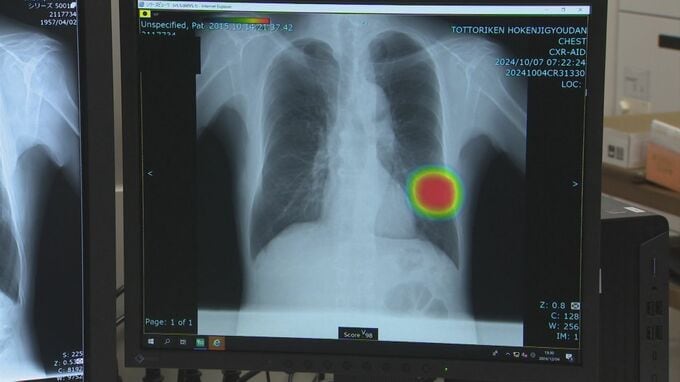

肺がん検診など胸部X線診断に「AI」導入 検診分野では中四国初 2024年12月11日(水) 11:57 鳥取 胸部X線画像に表れた異常を、人工知能・AIが強調して見せることで見落としを少なくするシステムを鳥取県保健事業団が導入し、検診の精度アップに繋がると期待されています。肺がんなどの早期発見のため検診など…